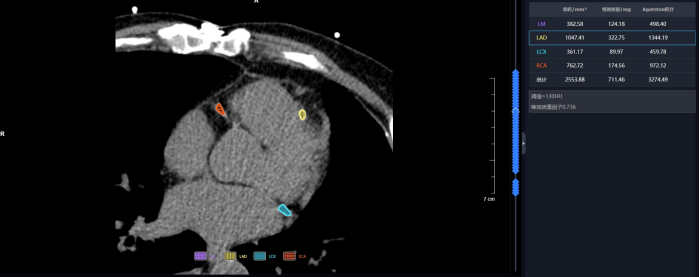

联影智能CT门控钙化积分智能分析系统可自动检出左主干(LM)、左前降支(LAD)、左回旋支(LCX)以及右冠状动脉(RCA)四大主支的钙化病灶并精准标记,智能计算各支血管的钙化积分值和总钙化积分值,支持自定义分支钙化灶编辑,自动生成智能报告,辅助医生对冠状动脉整体钙化程度进行量化评估,助力心血管疾病风险预测。

联影智能CT门控钙化积分智能分析系统能够为心血管疾病风险得评估和诊断提供支持。系统可精准检测并标记冠状动脉的钙化病灶、智能计算钙化积分,通过自动且精准的量化分析,助力医生提升诊断效率,降低漏诊风险。